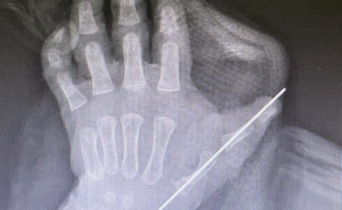

李甲、孙传伟手术团队为圆圆进行了专科检查,检查发现其左拇指掌指关节桡侧见一多指,多指呈两节;左副拇指较主拇指细短。双手各指色红润,皮肤无红肿破溃。

术前

术后即刻